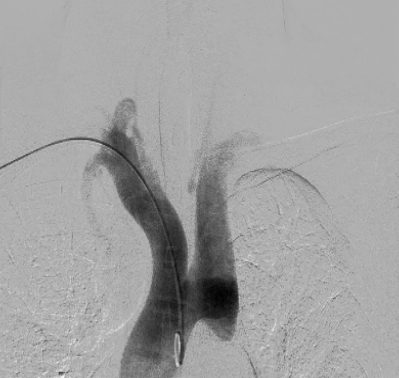

张文胜医生分享的病例题目为《主动脉弓离断患者急诊取栓一例》,患者是一名55岁的男性,因“突发失语伴左侧肢体乏力2小时余”到我院急诊就诊,急诊查颅脑CT未见出血,考虑急性脑梗死,患者接受了静脉溶栓治疗,同时桥接血管内介入治疗,在经右侧经股动脉路径行脑血管造影的过程中,发现猪尾巴导管和单弯导管均无法通过降主动脉,介入团队迅速更改介入路径为右侧桡动脉,主动脉弓造影证实了主动脉弓离断A型,进一步脑血管造影提示右侧颈内动脉末端闭塞,行血栓抽吸术成功开通闭塞的血管,术后患者恢复良好,未遗留明显的神经功能缺损。

脑血管造影提示主动脉弓离断